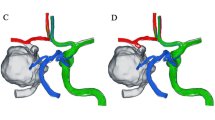

Ultrasound imaging was performed post-procedure to confirm the absence of complications, such as arterial stenosis or pseudoaneurysms (Fig. 1). Once successful suturing was verified, manual pressure was applied to the wound for 3 min. Continuous compression with an elastic bandage was not required. In cases where the initial attempt at hemostasis with the ProGlide device failed, a second attempt with the same device was avoided. This precaution was taken to minimize the risk of BA spasms, vascular injury, or additional procedural failure.

(A), Perclose ProGlide was implanted into the vessel along the guide wire until obvious pulsed blood flow was observed. (B), Held the handle to maintain the suture device 45°up, put up the lever and slightly pulled back the device until resistance is encountered and the bleeding was stopped. Stabilized the instrument and pushed the needle plunger to close the wound. (C), Pressed the wound for 3 min after suturing, no active bleeding or hematoma was observed at the puncture site. (D), Blood flow and vascular morphology was uninterrupted at the puncture site. No existence of artery stenosis, thrombosis and pseudoaneurysm under the check of ultrasonography.